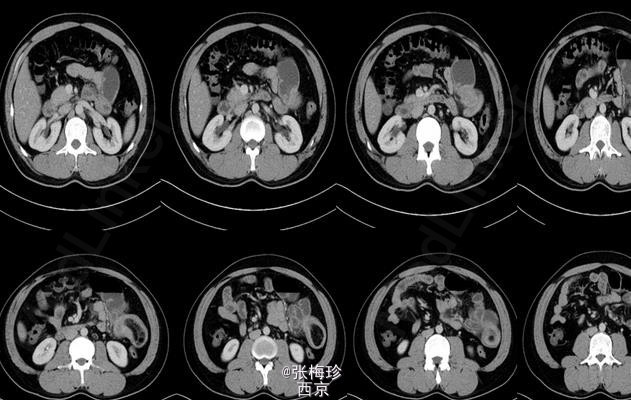

临床一例Meckel憩室

患者男性,30岁,2周前无明显诱因出现肚脐周围闷痛为绞痛伴恶心。

Meckel憩室 处理;手术治疗,解除梗阻并切除憩室

Meckel憩室及其并发症并无特殊的临床表现,与其他急腹症很难鉴别